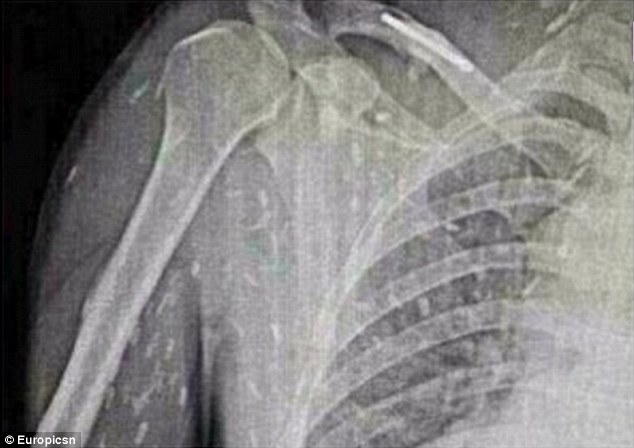

Τα σκουλήκια κυριολεκτικά κατέλαβαν το σώμα του. Όταν είδε τις ακτινογραφίες του, του κόπηκαν τα πόδια..

Όταν είδε τις ακτινογραφίες του, του κόπηκαν τα πόδια.. Σκουλήκια του έτρωγαν τα σωθικά και ο λόγος κάτι που πολλοί από εμάς τρώμε κάποιες φορές! – Εικόνα4 Μία μόλυνση από σκουλήκια-ταινίες μπορεί να οδηγήσει σε κυστικέρκωση. Αυτό συμβαίνει όταν τα σκουλήκια καταφέρνουν να μπουν στην κυκλοφορία του αίματος! Μετά μπορούν να πάνε στον εγκέφαλο, με κίνδυνο της ίδιας της ζωής του ασθενή.